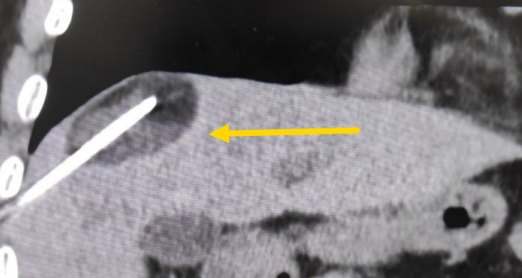

影像診療科陳寶瑩主任團(tuán)隊(duì)評(píng)估后指出,較大的腫瘤位于肝頂部緊貼膈肌,如果繼續(xù)發(fā)展,腫瘤很可能突破肝包膜侵犯到膈肌,建議及時(shí)干預(yù)。病變緊臨膈肌,如果要完全消融,膈肌損傷的可能性就比較大,與其他局部治療方式比較,冷凍消融對(duì)周?chē)K器、血管及神經(jīng)損傷的可能性較小、安全性更高、患者疼痛感較輕,建議通過(guò)CT精準(zhǔn)引導(dǎo)下經(jīng)皮微創(chuàng)冷凍消融治療。

這個(gè)患者病變位置刁鉆,穿刺難度大,冷凍消融的難點(diǎn)在于既要不損傷膈肌和肺組織,同時(shí)又要盡最大可能完全消融腫瘤。術(shù)前陳寶瑩主任、李鐵柱教授、兀云飛醫(yī)生詳細(xì)設(shè)計(jì)進(jìn)針路徑、布針計(jì)劃,術(shù)中微創(chuàng)團(tuán)隊(duì)協(xié)調(diào)配合,李鐵柱教授仔細(xì)操作,精準(zhǔn)到位,順利完成兩個(gè)病變的布針,遂啟動(dòng)治療,先快速降溫到-150多度,再升溫至15?,經(jīng)過(guò)兩個(gè)循環(huán)反復(fù),即刻觀察到病變完全被冰球覆蓋,同時(shí)周?chē)K器無(wú)損傷,術(shù)中患者幾乎沒(méi)有疼痛,還和醫(yī)生聊起了天。

CT精準(zhǔn)定位腫瘤

術(shù)中冰球形成